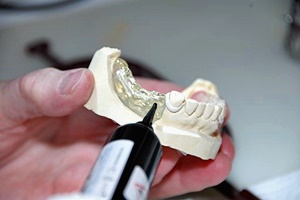

사랑니는 보통 큰 어금니와 비슷하게 생겼습니다. 사랑니의 형태나 크기는 매우 다양하다고 하는데요. 보통의 어금니 보다 깊이 나기 때문에 빼기 어렵거나 절개를 통해 힘들게 빼야 하는 경우가 많습니다. 원래 사랑니는 음식물을 갈아 내기 위한 용도라고 하는데요. 이것은 치아의 퇴화 현상이라고 생각하시는 분들도 많이 계십니다.